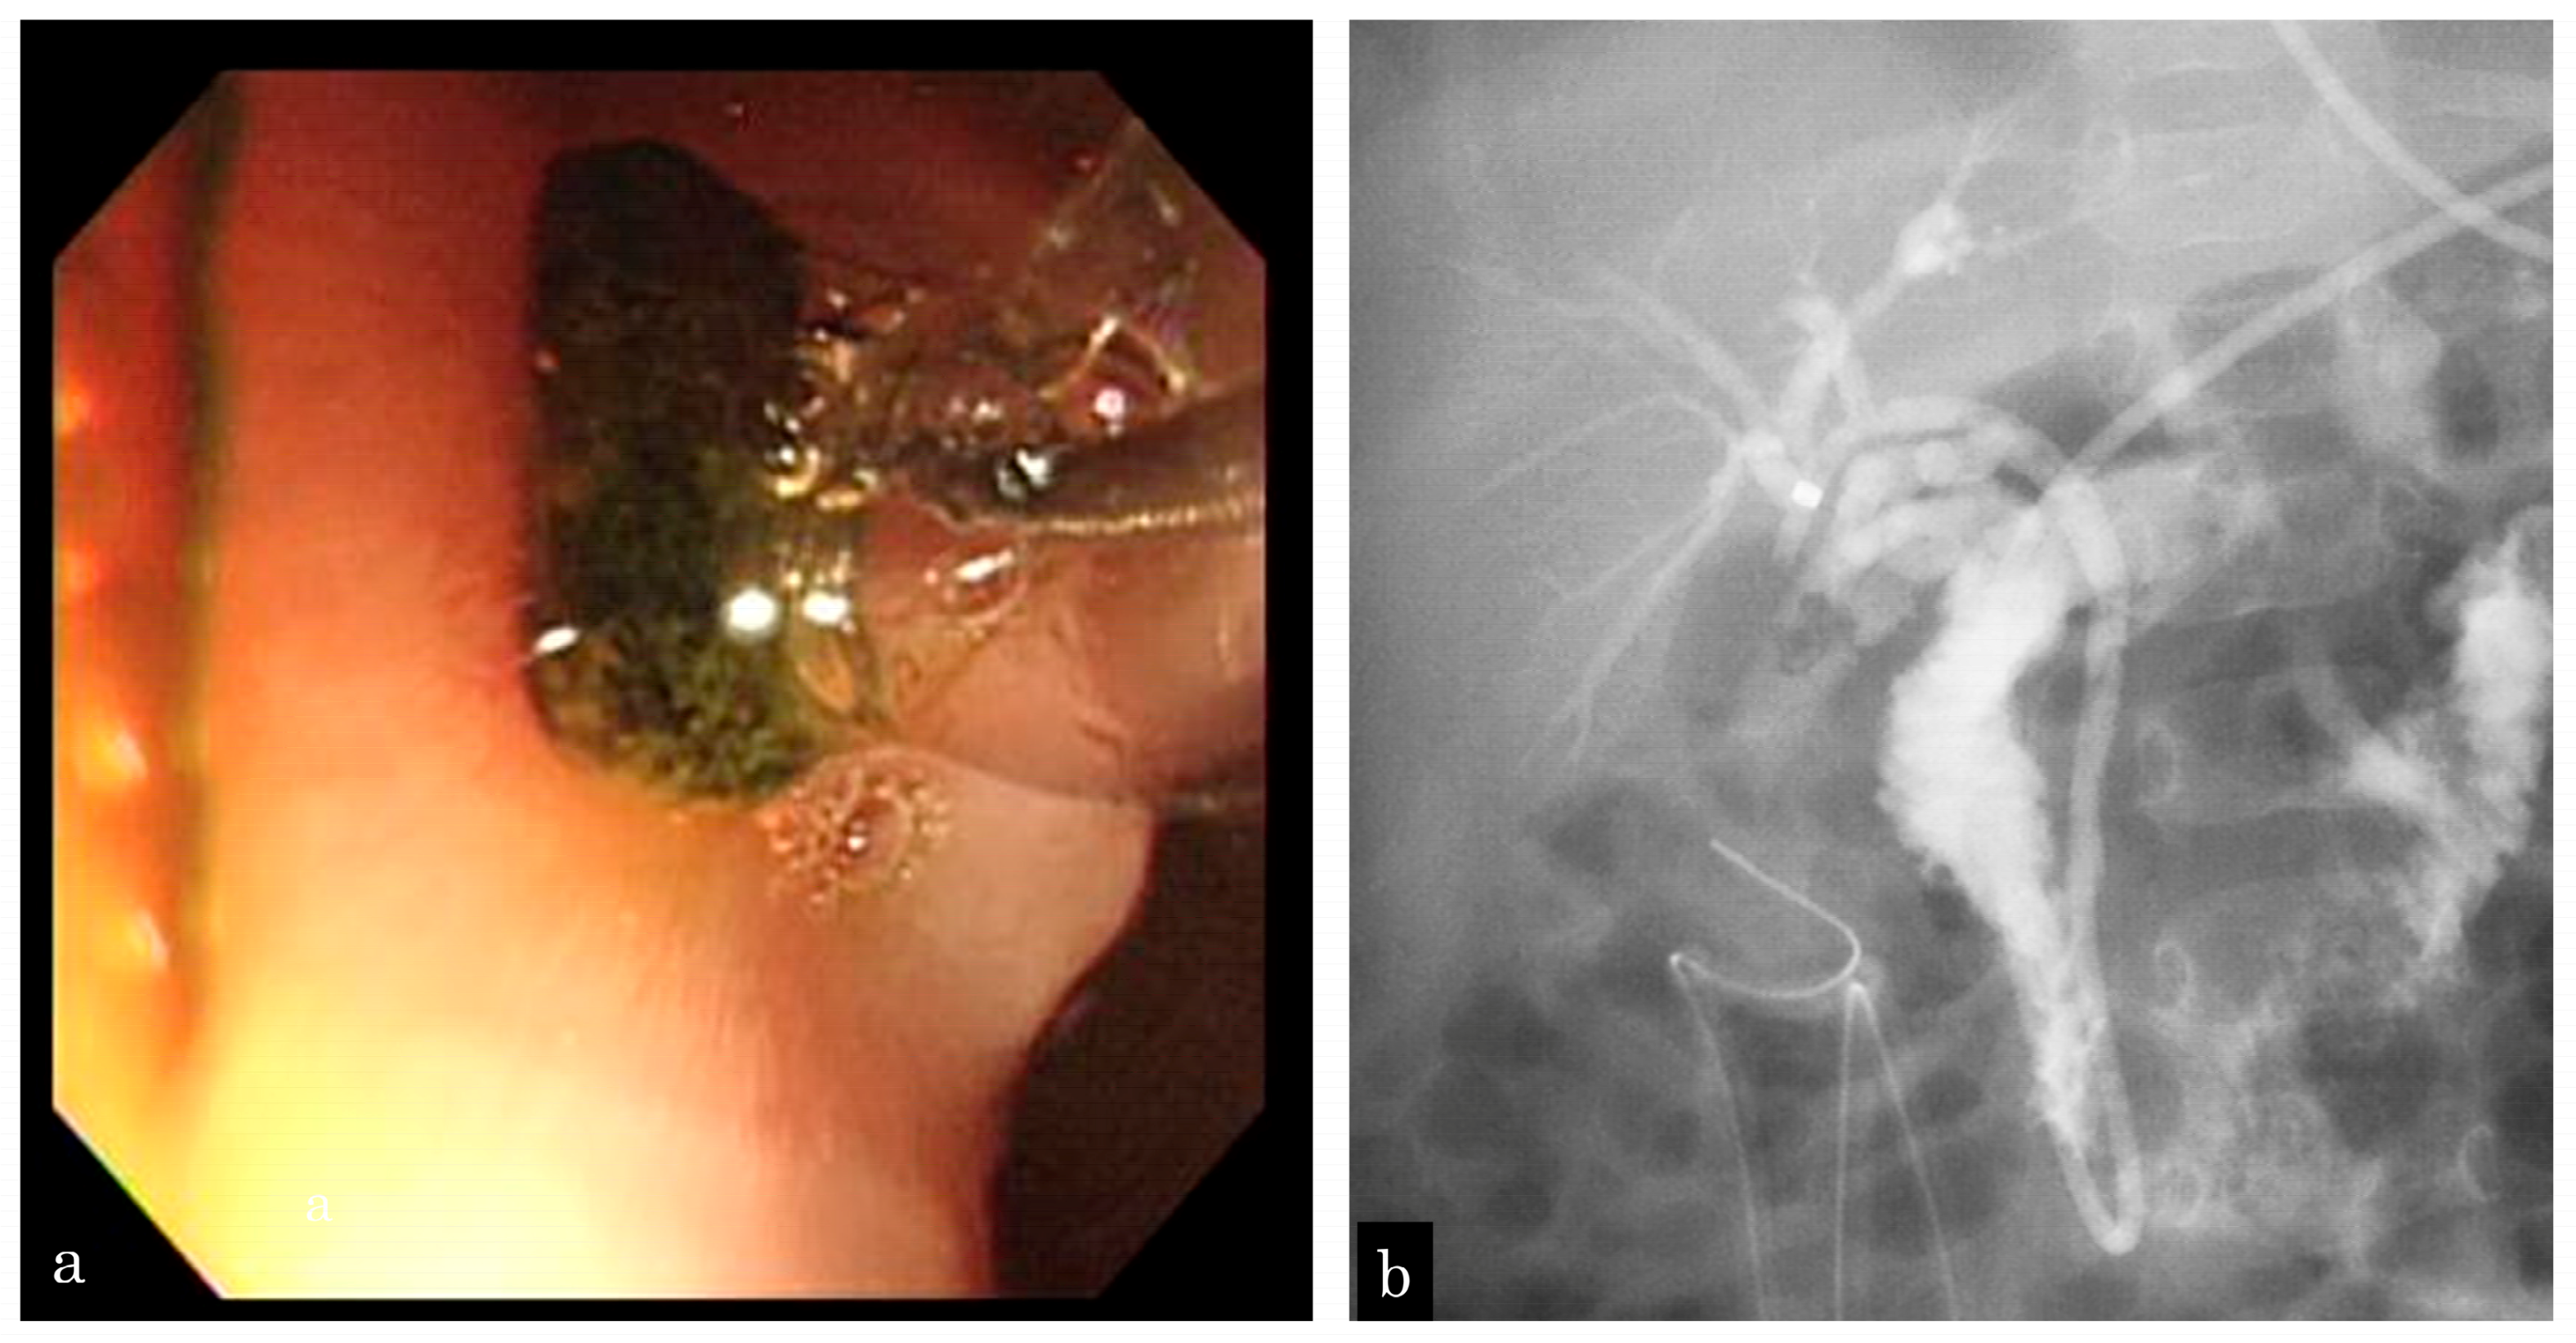

A 5-month-old girl presented with vomiting. Ultrasonography (US) revealed GBSs and gallbladder wall thickness. She presented with sepsis and urgently underwent gallbladder drainage (Figure 1a). During surgery, one CBDS impacting the distal common duct was observed, and an ENBD tube was inserted (Figure 1b). After recovery from cholecystitis and sepsis, EPBD was performed for CBDSs (Figure 2a,b). As the stone was 3 mm in size, the papilla was dilated by 3 mm in 30 s, and the stone was removed by one balloon pulling. The next day, after EPBD, serum lipase (normal range: 13–49 IU/L) levels increased to 1695 IU/L and returned to normal on the fifth day. After pancreatis improved, she underwent a cholecystectomy. The post-EPBD period was 4 months, and her clinical course was uneventful.

Figure 2.

A 5-month-old girl who presented with vomiting and revealed gallbladder and common bile duct stones on ultrasonography. (a) EPBD is performed following recovery from cholecystitis and sepsis, and the stone is removed by one balloon pulling. (b) Following EPBD, a 5-Fr prophylactic ENBD tube is inserted, and no residual stone is revealed by cholangiography.